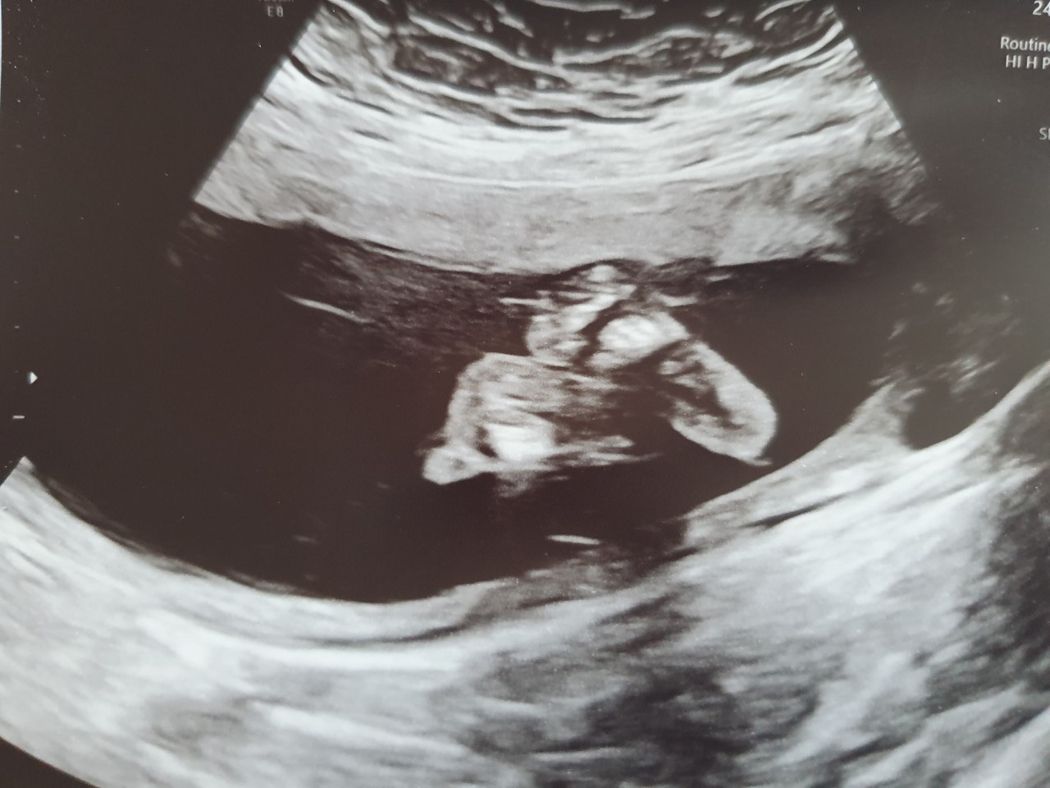

Thankfully, nothing went wrong, and Danielle is now 24 weeks pregnant with a baby girl.

“For the first few weeks I was so nervous, but now I'm excited," she said.

She added: “It felt amazing to see her heart beat for the first time and my little girl is giving me a hard time with all the kicking. She's always booting me – but I wouldn't have it any other way."